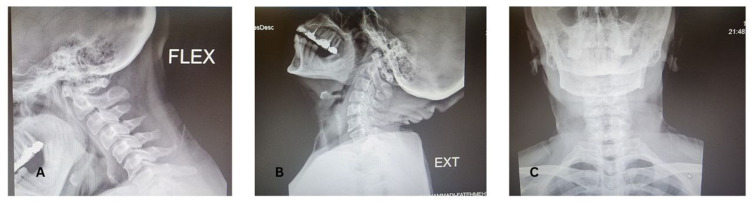

Background: Arnold-Chiari Malformation Type I (ACM-I) is a congenital disorder that can lead to severe neurological symptoms. While decompression surgery is the standard treatment, postoperative complications such as cerebrospinal fluid (CSF) leakage and infections can result in critical outcomes. Here, we report a case of septic shock following decompression surgery in a patient with ACM-I, emphasizing the challenges in postoperative critical care management.

Case presentation: A 45-year-old woman with rheumatoid arthritis and progressive neurological symptoms underwent decompression surgery for ACM-I. On postoperative day five, CSF leakage was noted at the surgical site, accompanied by fever and leukocytosis. Despite broad-spectrum antibiotics, the patient developed septic shock, requiring mechanical ventilation and vasopressor support. CSF cultures revealed Acinetobacter baumannii infection, necessitating surgical debridement and intrathecal colistin. Despite aggressive management, the patient succumbed to septic shock.